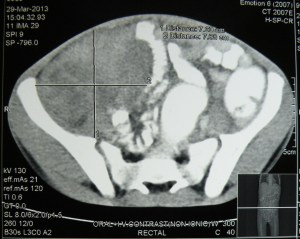

12.4.14 Presented a case of ‘mesenteric fibromatosis’ in the clinical meeting held in the medical education cell of the college. An 11 years old child was shifted from paediatrics ward, with a history of fever but was found to be having a big palpable mass in the right iliac fossa. A CT scan showed a 10 cm big well-defined mass in the peritoneal cavity. At operation, the mass was found to be arising from the mesentery of the distal ileum. The mass and the adherent loop of ileum were resected. Biopsy revealed an aggressive fibromatosis of the mesentery.

Mesenteric fibromatosis presenting as a diagnostic dilemma: a rare differential diagnosis of right iliac fossa mass in an eleven year old-a rare case report.Mahajan A1, Singh M1, Varma A1, Sandhu GS1, Singh M1, Nagori R1.

Journal of Clinical and Diagnostic Research. 2015 Nov, Vol-9(11): PJ01-PJ02